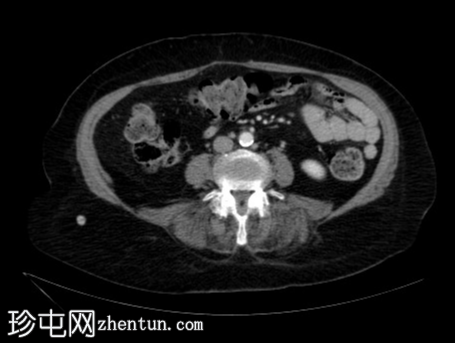

轴向C+门静脉期

胃食管连接处及大部分胃已疝入胸腔。

胃沿其长轴旋转。

无胃扩张或壁异常强化征象。

检查结果提示胃扭转疝入裂孔,无急性梗阻征象(不完全性)。

胃扭转有两种类型:

器质轴型:沿其长轴旋转,多见于成人

肠系膜轴型:沿其短轴旋转,多见于儿童